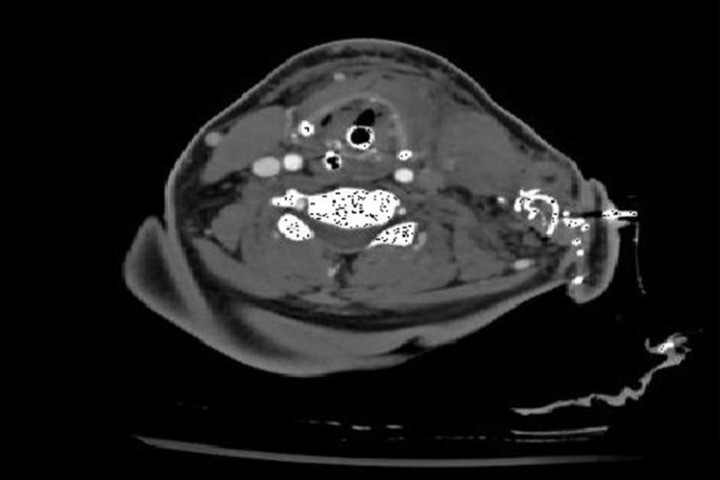

"Во второй половине 2016 года в Травмпункт Купер в Камдене, Нью-Джерси, США, поступила 44-летняя женщина с 25 проникающими ранениями в область груди и шеи. Когда пациентка поступила в больницу, она была без сознания, систолическое кровяное давление держалось на отметке 70. Пациентка была быстро осмотрена, было сделано переливание 4 единиц красных кровяных телец и 6 единиц свежей замороженной плазмы. Во время осмотра терапевты обнаружили два ранения в нижней части шеи в одном сантиметре над ключицей, кровотечение из этих ранений было неконтролируемым. Ранение было перевязано бинтом Combat Gauze, но бинт сразу же пропитался кровью. Пропитанный кровью бинт был удален и на оба ранения было помещено одно устройство iTClamp. Терапевты заметили, что кровь протекала и вокруг устройства. iTClamp было удалено, раны перевязали бинтом, а затем снова использовали iTClamp для изоляции раны. Врачи отметили, что сочетание бинта и iTClamp позволило им уменьшить площадь раны и закрыть кожу, что привело к хорошему гемостазу (рисунок 1). Все действия по остановке кровотечения заняли меньше двух минут, а сочетание материалов позволило врачам запечатать обе опасные раны. Состояние пациентки стабилизировалось, она была отправлена на компьютерную томографию для дальнейшего обследования. Возможность выполнить компьютерную томографию до оперативного вмешательства позволила хирургу оценить потенциальные зоны кровотечения и определить, откуда начинать хирургическое исследование 25 ран. Не было отмечено практически никакого рассеяния (за исключением небольшого рассеяние от шовных игл) и даже меньше, чем рассеяние от скоб (рисунки 2 и 3). После подтверждения отсутствия артериального кровотечения врачи сконцентрировались на ранах и переместили пациентку в операционную. Хирурги смогли провести подготовку к операции с зафиксированным устройством и сняли iTClamp перед началом хирургического исследования. Хирурги открыли близкие к ключице раны и исследовали их вглубь до ключицы, чтобы перевязать первую ветвь подключичной вены."

Рисунок 2

Другим интересным моментом, который заслуживает дальнейшего обсуждения, является тот факт, что компьютерная томография показала очень небольшое количество линейных артефактов или рассеяния от устройства iTClamp. Проблема линейных артефактов от металлических структур или скоб не нова, и хотя существуют программы для коррекции этой проблемы, они могут быть не всегда доступны, или же увеличение жесткости излучения до показателей выше среднего делают коррекцию невозможной.

Одним из способов решения этой проблемы является итерационная реконструкция, однако, если металл блокирует все фотоны, информация из мягких тканей не может быть запрошена с коррекцией рассеяния. Несмотря на то, что в iTClamp есть восемь металлических игл, доктор в отчете о случае заметил, что практически никакого рассеяния не было обнаружено, и рассеяние было даже меньше, чем от скоб. Это информация определенно гарантирует будущие обсуждения и исследования, так как возможность быстро останавливать кровотечение и поддерживать целостность компьютерной томографии имеет преимущества, особенно в обработке ран, где время имеет огромное значение.

Рисунок 3